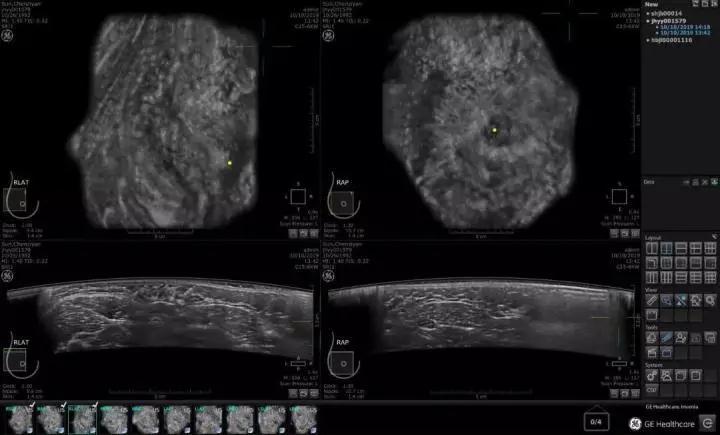

2012年9月26日,美国 FDA (食品药品监督管理局)批准了第一台用于乳腺癌筛查的超声设备。根据临床试验,应用ABUS超声系统进行读片比单独阅读乳腺钼靶摄片显著增加了乳腺癌的检出率,更适用于那些乳腺组织致密、钼靶摄片阴性且无乳腺癌症状的女性。到2019年10月,美国GE医疗推出全新一代的ABUS乳腺癌筛查系统,成为一款真正意义上适合中国乳腺癌标准化大规模的设备,它的优势在于:

02 更精准的图像

15CM宽视野弧形探头,每秒300万像素的图像采集,毫无遗漏对全乳腺超声断层扫描(类CT),3D全容积成像,不依赖操作者的手法,全自动数据采集。图像数据存储云端,医生可多次读片,作前后图像数据对比。能帮助大量无病灶人群找到0.2cm以上微小病变组织。